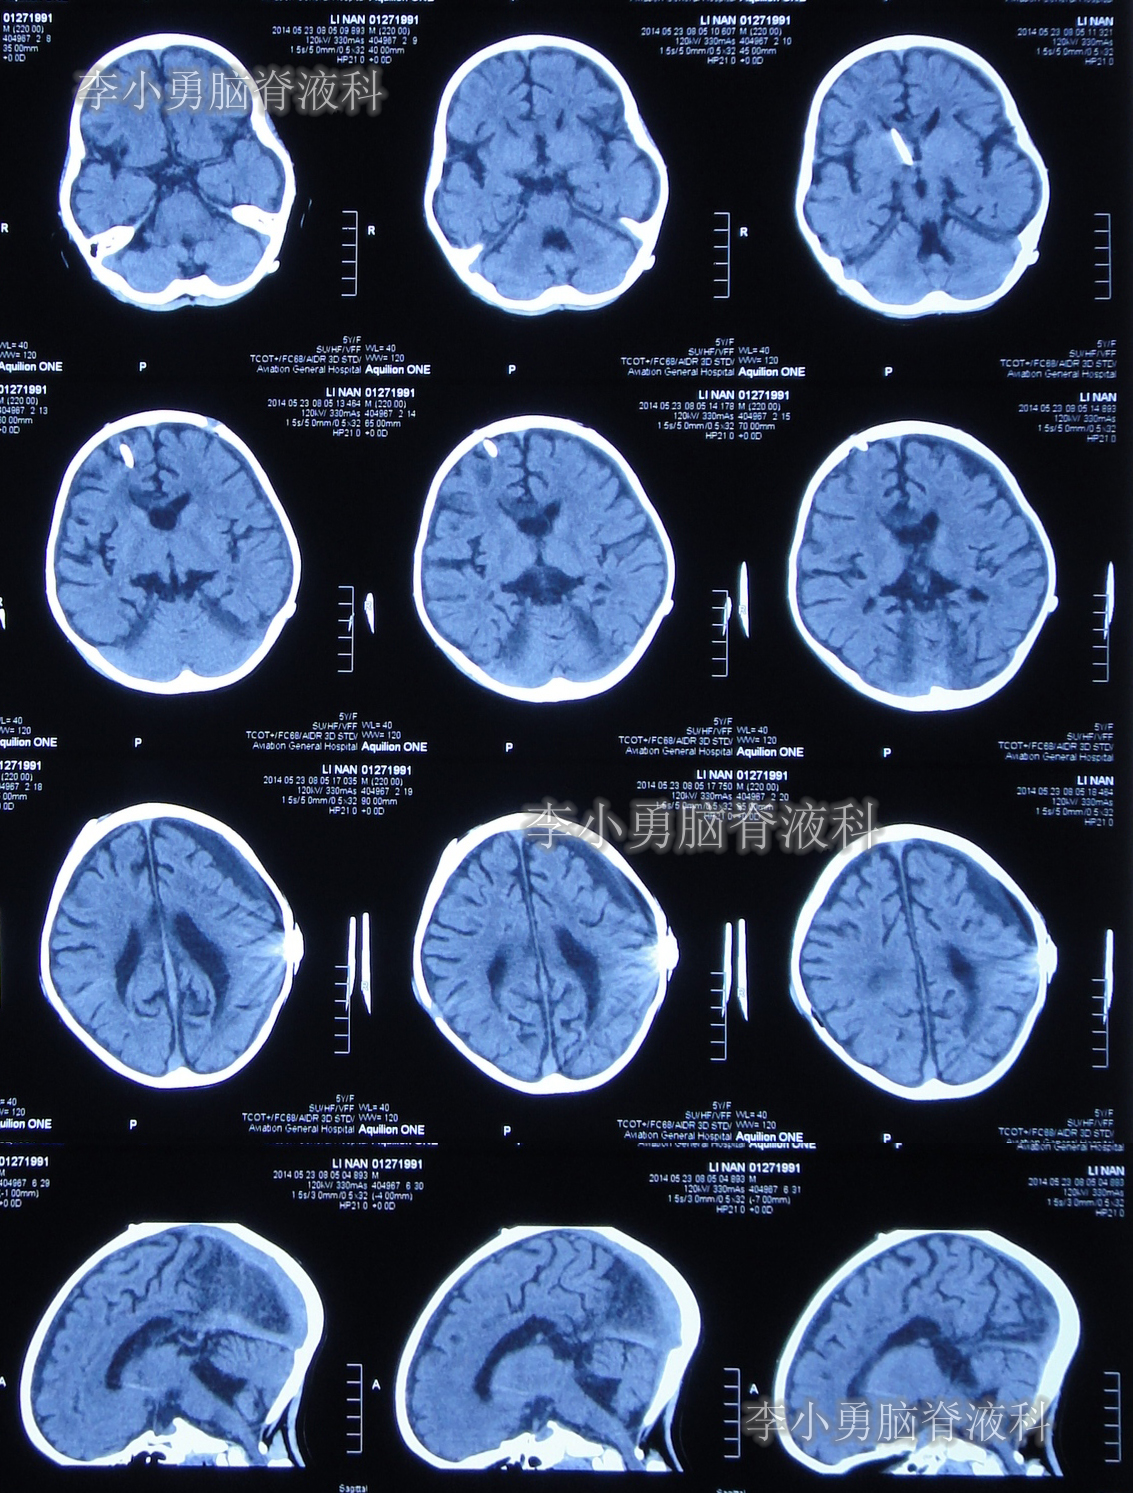

数天之后即在2013年9月2日,为治疗脑积水,患儿至河南省郑州市某三甲医院神经外科就诊,当日头颅CT示严重脑积水并第四脑室扩张严重(图-1);当天收入院。在住院后次日即2013年9月3日,进行了右侧额角脑室腹腔分流术。

图-1:2013年9月2 日头颅CT

当天头颅CT示第四脑室包括在内的脑室系统全部显著扩张的表现(图-5)。

图-5:2014年3月17日入院时头颅CT

住院治疗第2天即2014年3月19日,复查头颅CT示第四脑室包括在内的脑室系统扩张程度虽均有所减轻,但第四脑室扩张程度仍严重(图-7)。

图-7:2014年3月19日头颅CT